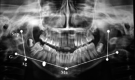

Materials and method: Fifteen patients of prospective study design were selected for study. This study was undertaken to evaluate the mandibular ramal growth in TMJ ankylosis patients treated without growth center transplantation using orthopantomogram as a tool of assessment.

Results: Mean ramal length of the operated right side was found to be 42.02 mm in immediate postoperative, 43.18 mm in sixth month postoperative and 44.57 mm in 1 year postoperative follow-up. Mean ramal length of the operated left side was found to be 40.15 mm in immediate postoperative, 42.10 mm in sixth month postoperative and 44.80 mm in 1 year postoperative follow-up.

Conclusion: Our investigations showed that mandibular growth rate increases after successful treatment of ankylosis in children. One drawback of this treatment protocol that we observed was that the total growth deficit manifested in all our patients could not be made up.